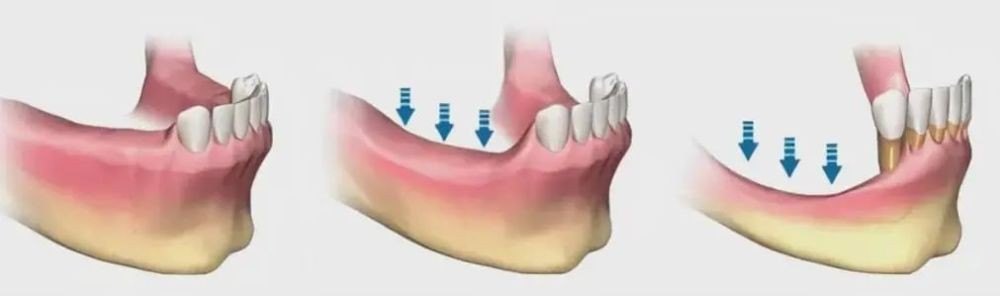

5、牙槽骨萎缩

活动假牙不像真牙有独立的牙根,因此在长期的使用中,无法对牙龈和牙槽骨产生良性的刺激,从而导致牙槽骨继续萎缩。